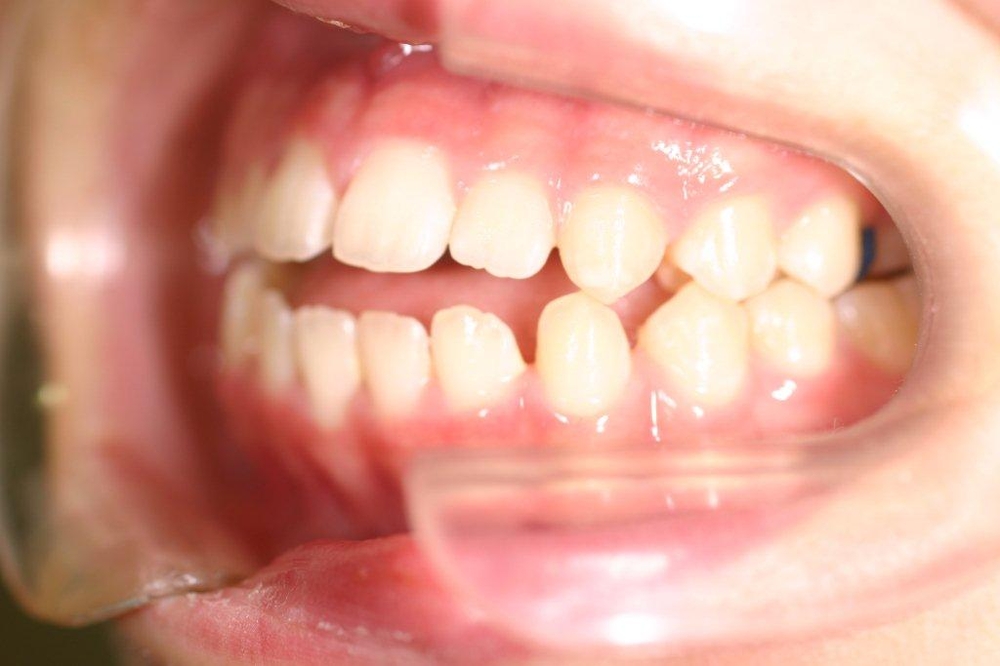

叢生の抜歯矯正の症例

Before

After

叢生ケースで4番の歯を4本抜歯し、唇側ブラケット矯正にて治療をした

年齢 30代

治療期間 2年6ヶ月

治療費用 1,000,000円

治療のリスク 特になし